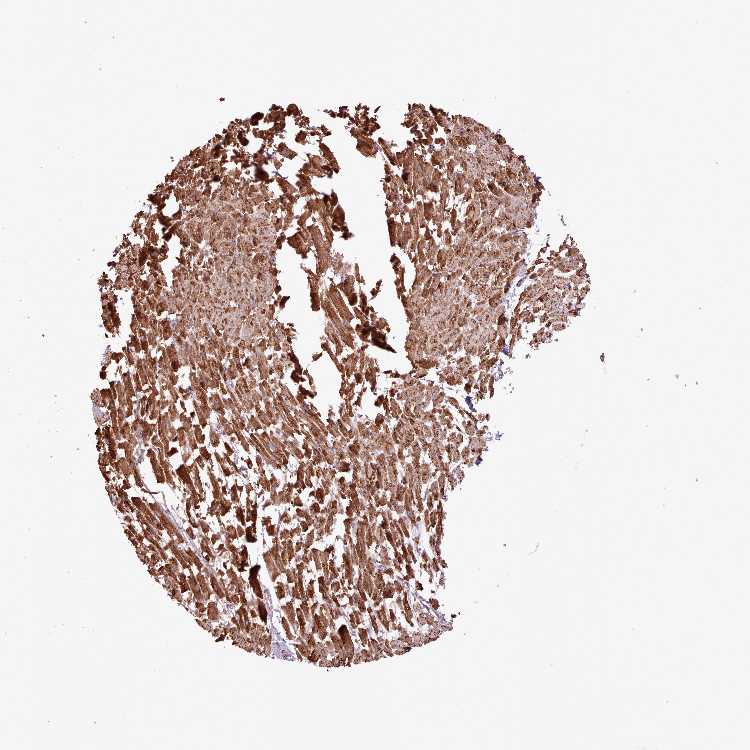

HEART MUSCLE - Antibody stainingi

Antibody staining in the annotated cell types in the current human tissue is reported as not detected, low, medium, or high, based on conventional immunohistochemistry profiling in selected tissues. This score is based on the combination of the staining intensity and fraction of stained cells.

Each image is clickable and will lead to virtual microscopy that enables deeper exploration of all samples and also displays staining intensity scores, fraction scores and subcellular localization as well as patient and tissue information for each sample.

Antibody HPA051118

Cardiomyocytes High